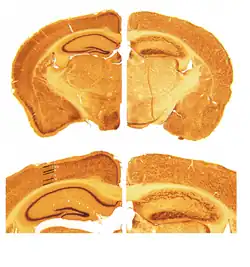

Das Gehirn von Reeler-Mäusen unterscheidet sich makroskopisch und mikroskopisch bedeutend von dem normaler Mäuse. Das Kleinhirn ist deutlich in seiner Größe reduziert (ca. −30 %) und zeigt bei mikroskopischer Betrachtung nicht die typische Laminierung in unterschiedliche Zellschichten. Die Großhirnrinde (lat. Cortex) und der Hippocampus sind ebenfalls stark in ihrer zellulären Architektur verändert. Während im normalen Gehirn der Cortex üblicherweise in sechs Schichten unterteilt werden kann, schien es anfangs so, als sei diese Schichtung bei Reeler-Mäusen völlig aufgehoben.[10]

Es wurde jedoch gezeigt, dass die kortikale Schichtung bei der Reeler-Maus keinesfalls komplett aufgehoben ist, sondern dass sie vielmehr auf dem Kopf steht.[11] D. h. Nervenzellen, die normalerweise in den tiefen Schichten des Cortex liegen, finden sich in der Reeler-Maus weiter in Richtung Hirnoberfläche und umgekehrt. Dieses Phänomen steht in direktem Zusammenhang mit der Funktion des „Reelin“-Proteins während der embryonalen Entwicklung. Obwohl über den genauen Modus in Fachkreisen noch gestritten wird, ist allgemein anerkannt, dass Reelin als Signalmolekül die Wanderung von Neuronen während der Entwicklung des Gehirns beeinflusst. Die Abwesenheit von Reelin im Hirn der Reeler-Maus führt daher zu gestörter neuronaler Migration.